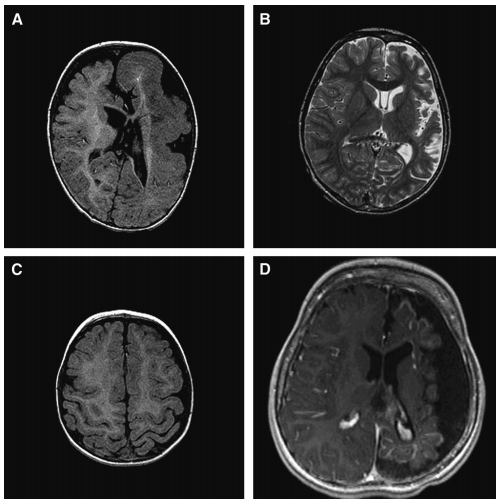

Imaging surgical epilepsy in children( 儿童癫痫手术 影像) 英文原文摘要: Abstract Introduction Epilepsy surgery rests heavily upon magnetic resonance imaging (MRI). Technical develop...

局灶性MRI异常增加了术前拟手术 治疗癫痫患者 的致痫区成功勾画的机会(Duncan和Sagar, 1987;Fish等人,1993年;斯宾塞,1995;艾蒙等,1996;Cascino, 2004;Tonini等人,20...